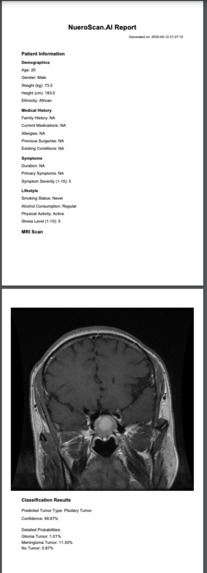

NeuroScan.AI is an advanced brain tumor classification system that: Analyzes MRI scans using deep learning Classifies different types of brain tumors with 92% accuracy Generates comprehensive medical reports Provides personalized treatment recommendations using Google's Gemini AI Creates detailed PDF reports with patient information, analysis results, and treatment plans Includes a section for doctor's review and approval

We built NeuroScan.AI using a sophisticated tech stack: Deep Learning: TensorFlow 2.15.0 with MobileNetV2 architecture Web Interface: Streamlit 1.32.0 for the user-friendly web application Image Processing: OpenCV 4.9.0.80 and Pillow 10.2.0 AI Integration: Google's Gemini AI for treatment recommendations Report Generation: FPDF2 for creating professional medical reports Data Processing: NumPy 1.24.3 and scikit-learn 1.4.1 The system was trained on a comprehensive dataset of brain MRI scans, fine-tuning the MobileNetV2 model to achieve optimal performance.